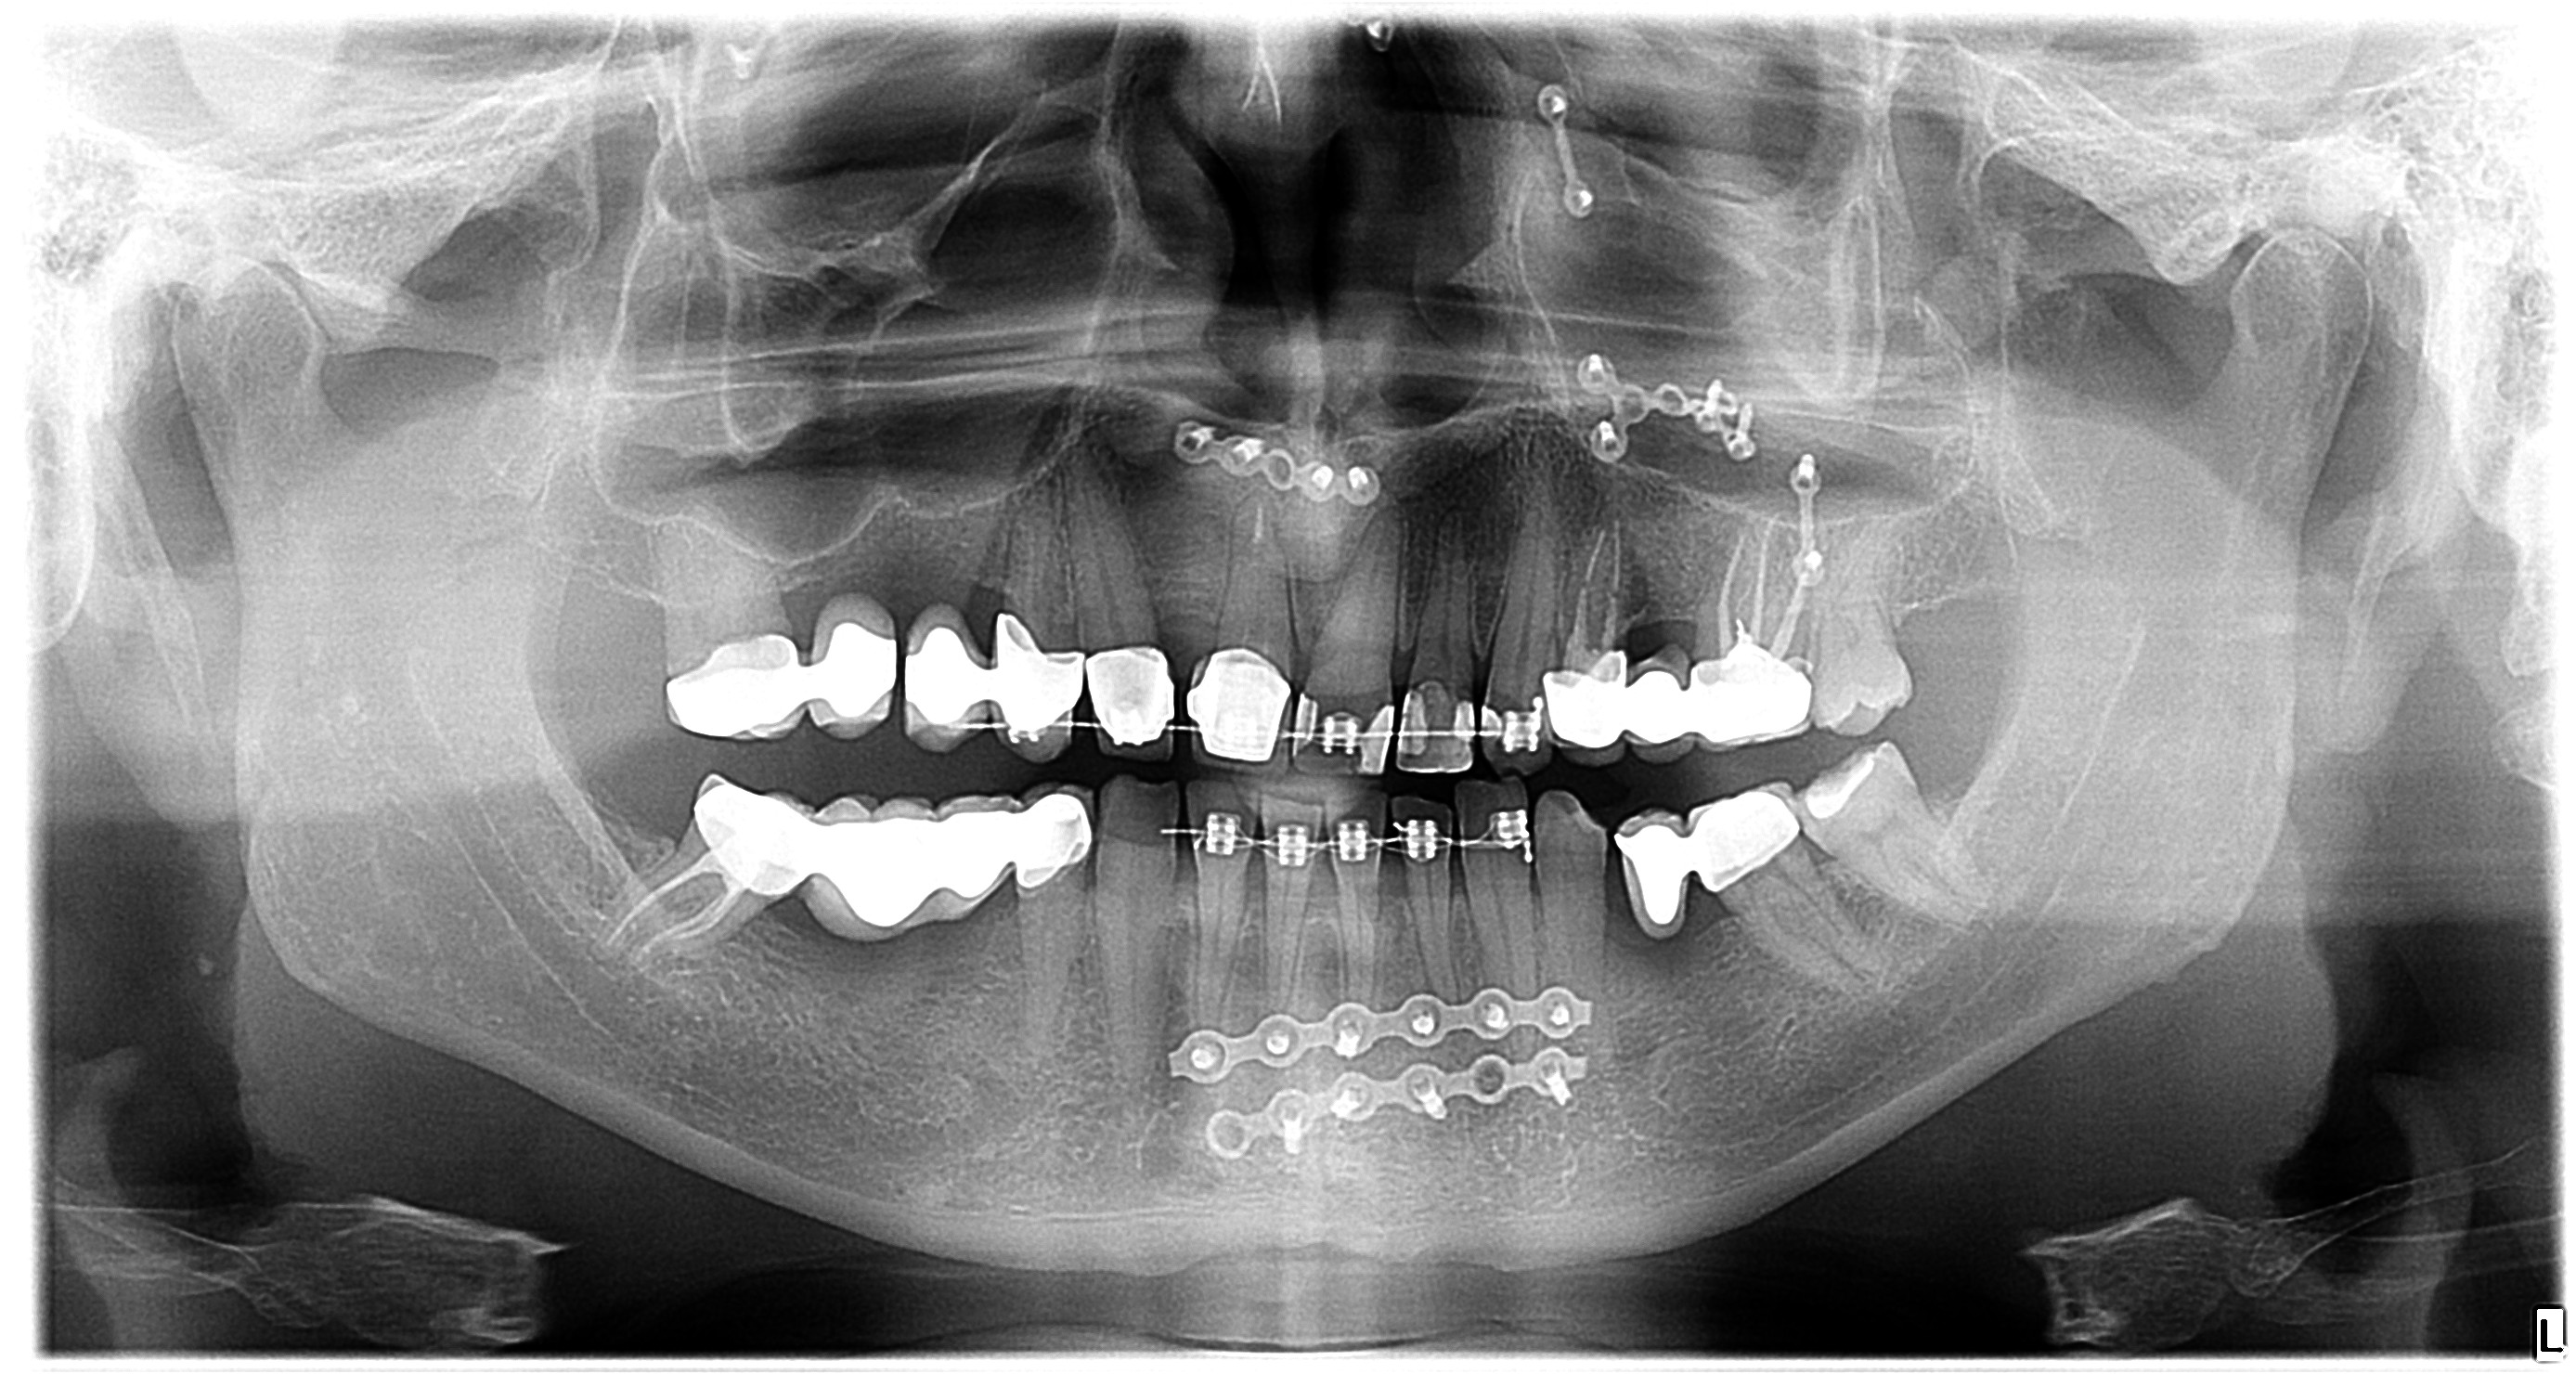

Digitalna tehnologija je unaprijedila medicinske dijagnostičke postupke, a to se posebno odnosi na stomatološku praksu. Kada je riječ o dentalnom rendgenu, digitalni ortopan predstavlja značajan napredak u odnosu na tradicionalne rendgenske snimke. Evo nekoliko ključnih prednosti digitalnog ortopana u odnosu na klasične snimke:

Digitalni ortopan omogućuje visoku razlučivost slike, što znači da stomatolozi mogu dobiti vrlo detaljan prikaz svih zubnih struktura i okolnih tkiva. To je od iznimne važnosti jer precizna dijagnostika pomaže u otkrivanju čak i najmanjih problema s oralnim zdravljem.

Digitalni ortopan dolazi s dodatnim funkcijama obrade slike, kao što su povećavanje i mjerenje. To omogućuje stomatolozima da pažljivo analiziraju i procjenjuju podatke, što može dovesti do preciznije dijagnostike i planiranja liječenja.

Digitalni ortopan predstavlja značajan napredak u stomatološkoj dijagnostici u odnosu na tradicionalne rendgenske snimke. Njegovo korištenje pridonosi unaprjeđenju oralnog zdravlja pacijenata i omogućuje bolje planiranje i provođenje stomatoloških tretmana.